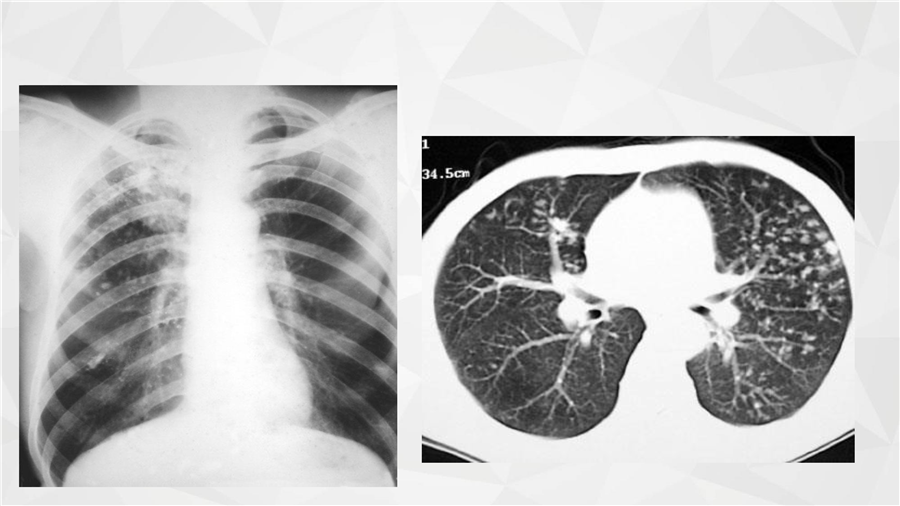

呼吸系统三